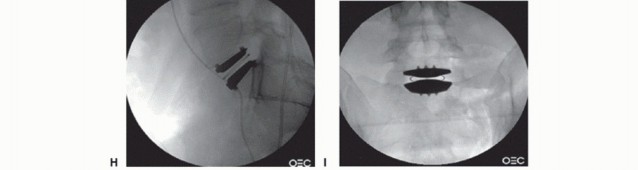

- TECH FIG 5 • A. True AP fluoroscopic image. The distance between the midpoint of the vertebra and the pedicles should be the same. The cortical margins of the pedicles themselves should be the same size (ensuring the spine is not rotated). Finally, the spinous processes should bisect the vertebra. The spinous processes are the least reliable landmark as they can be malformed, especially at L5 and S1. B. A sizing guide, or “lollipop,” demonstrates how well the endplate will be covered by the final implant. The largest size that allows good peripheral endplate coverage in both the sagittal and coronal planes is desired. C-E. Using radiolucent trial wedges of varying height and lordosis allows the final device to be individualized to the patient's anatomy. F. Introduction of the channel cutter into the disc space. G. Lateral fluoroscopic image showing implant insertion. The insertion instruments are still connected, which allows for fine adjustment to the final positioning. H,I. Lateral and AP fluoroscopic images of the final TDR placement with all of the instruments removed. The final implant should be in the center of the vertebral

body on the AP image and in the center (sagittal midline) or just posterior to the center of the vertebral body on the lateral image. (B-E: Courtesy of DePuy Spine, Raynham, MA.)

An implant-specific chisel is then directed straight posteriorly through the bodies to cut a groove for the keel or teeth that align the implant and prevent rotation (TECH FIG 5F) and the final implant inserted (TECH FIG 5G-I).